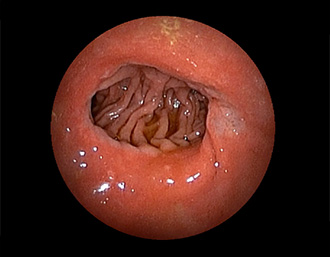

症例1:胃潰瘍(37才、男性)

①胃潰瘍(Stage A1)

健診:胃レントゲン検査で、胃角部ニッシェを指摘され当院受診。

胃角部小弯に、深くて大きな、大きさ約10mmの胃潰瘍(stage 1)

があり、潰瘍底は一部白苔はみ出しを認める。エソメプラゾールマグネシウム水和物投薬で治療開始しました。

(FICE+インジゴカルミン散布画像)